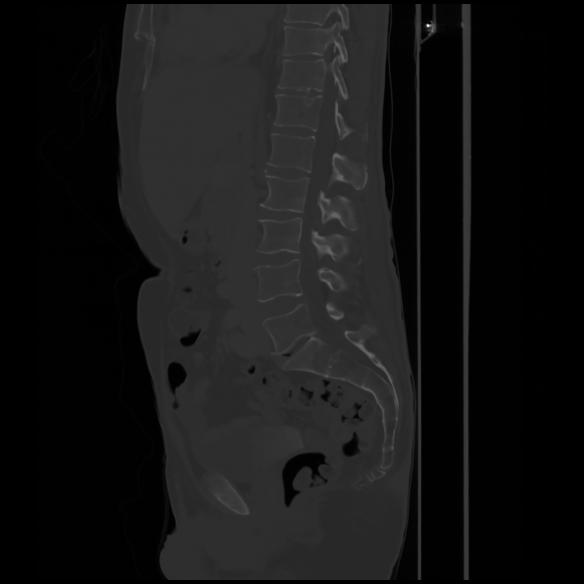

7 CUERPO,CE,Sagittal,3.000,CUERPO,Sagittal,